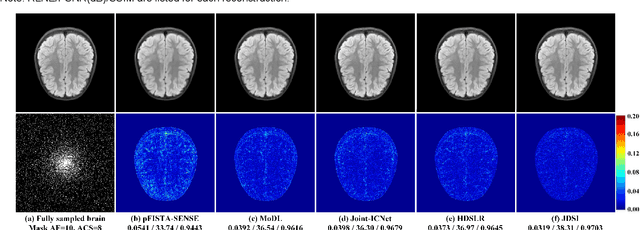

Abstract:Recent deep learning is superior in providing high-quality images and ultra-fast reconstructions in accelerated magnetic resonance imaging (MRI). Faithful coil sensitivity estimation is vital for MRI reconstruction. However, most deep learning methods still rely on pre-estimated sensitivity maps and ignore their inaccuracy, resulting in the significant quality degradation of reconstructed images. In this work, we propose a Joint Deep Sensitivity estimation and Image reconstruction network, called JDSI. During the image artifacts removal, it gradually provides more faithful sensitivity maps, leading to greatly improved image reconstructions. To understand the behavior of the network, the mutual promotion of sensitivity estimation and image reconstruction is revealed through the visualization of network intermediate results. Results on in vivo datasets and radiologist reader study demonstrate that, the proposed JDSI achieves the state-of-the-art performance visually and quantitatively, especially when the accelerated factor is high. Additionally, JDSI owns nice robustness to abnormal subjects and different number of autocalibration signals.